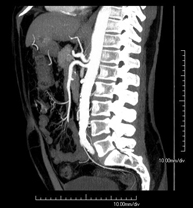

Prueba diagnóstica no invasiva que consiste en el estudio de la arteria aorta abdominal obteniendo imágenes de alta definición anatómica mediante el empleo de un equipo de TC (Tomografía Computarizada) y de contraste yodado. La calidad de las imágenes permite realizar reconstrucciones en 2D y 3D gracias a estaciones de trabajo especializadas en el estudio arterial. Está indicado en aquellos pacientes con enfermedad vascular (aterosclerosis), en aneurismas de aorta, en pacientes con dolor abdominal de posible origen vascular, en estudios pre-quirúrgicos de lesiones adyacentes a la aorta abdominal como "mapa" vascular, etc. La información obtenida de forma no invasiva es indispensable para los pacientes que requieren tratamiento percutáneo o quirúrgico. En aquellos pacientes que solo requieren un seguimiento de las lesiones vasculares, esta técnica es la técnica no invasiva de elección junto con la angio-RM. - Angio-TC arterias renales

Prova diagnòstica no invasiva que consisteix en l'estudi de l'artèria aorta abdominal amb l'obtenció d'imatges d'alta definició anatòmica mitjançant l'ús d'un equip de TC (Tomografia Computaritzada) i contrast iodat. La qualitat de les imatges permet realitzar reconstruccions en 2D i 3D gràcies a estacions de treball especialitzades en l'estudi arterial. Està indicat en aquells pacients que pateixen malaltia vascular (arteriosclerosi), aneurismes d'aorta, en pacient amb dolor abdominal d'un possible origen vascular, en estudis prequirúrgics de lesions adjacents a l'aorta abdominal com el "mapa" vascular, etc. La informació obtinguda de forma no invasiva és indispensable per als pacients que requereixen tractament percutani o quirúrgic. En aquells pacients que només requereixen un seguiment de les lesions vasculars, aquesta tècnica és la tècnica no invasiva d'elecció juntament amb l'angio RM. - Angio TC d'artèries renals